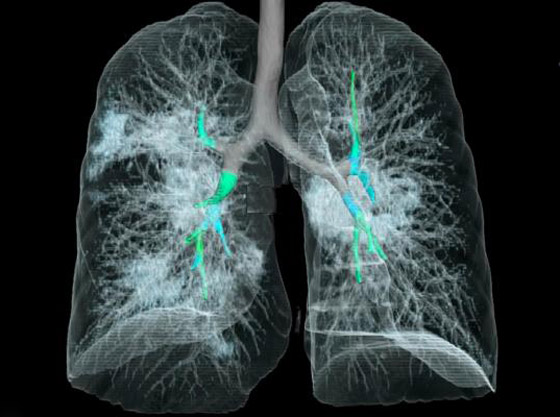

تصوير مقطعي محوسب من مستشفى جامعة جورج واشنطن يُظهر آثار فيروس كورونا المستجد، أو ما يُعرف بـ"كوفيد-19"  رئتي رجل عمره 59 عاماً. فشاهدوا معنا في الفيديو المدهش أدناه كيف تبدو رئة مصاب بفيروس كورونا (فيروس كوفيد 19) وما يحصل داخلها..